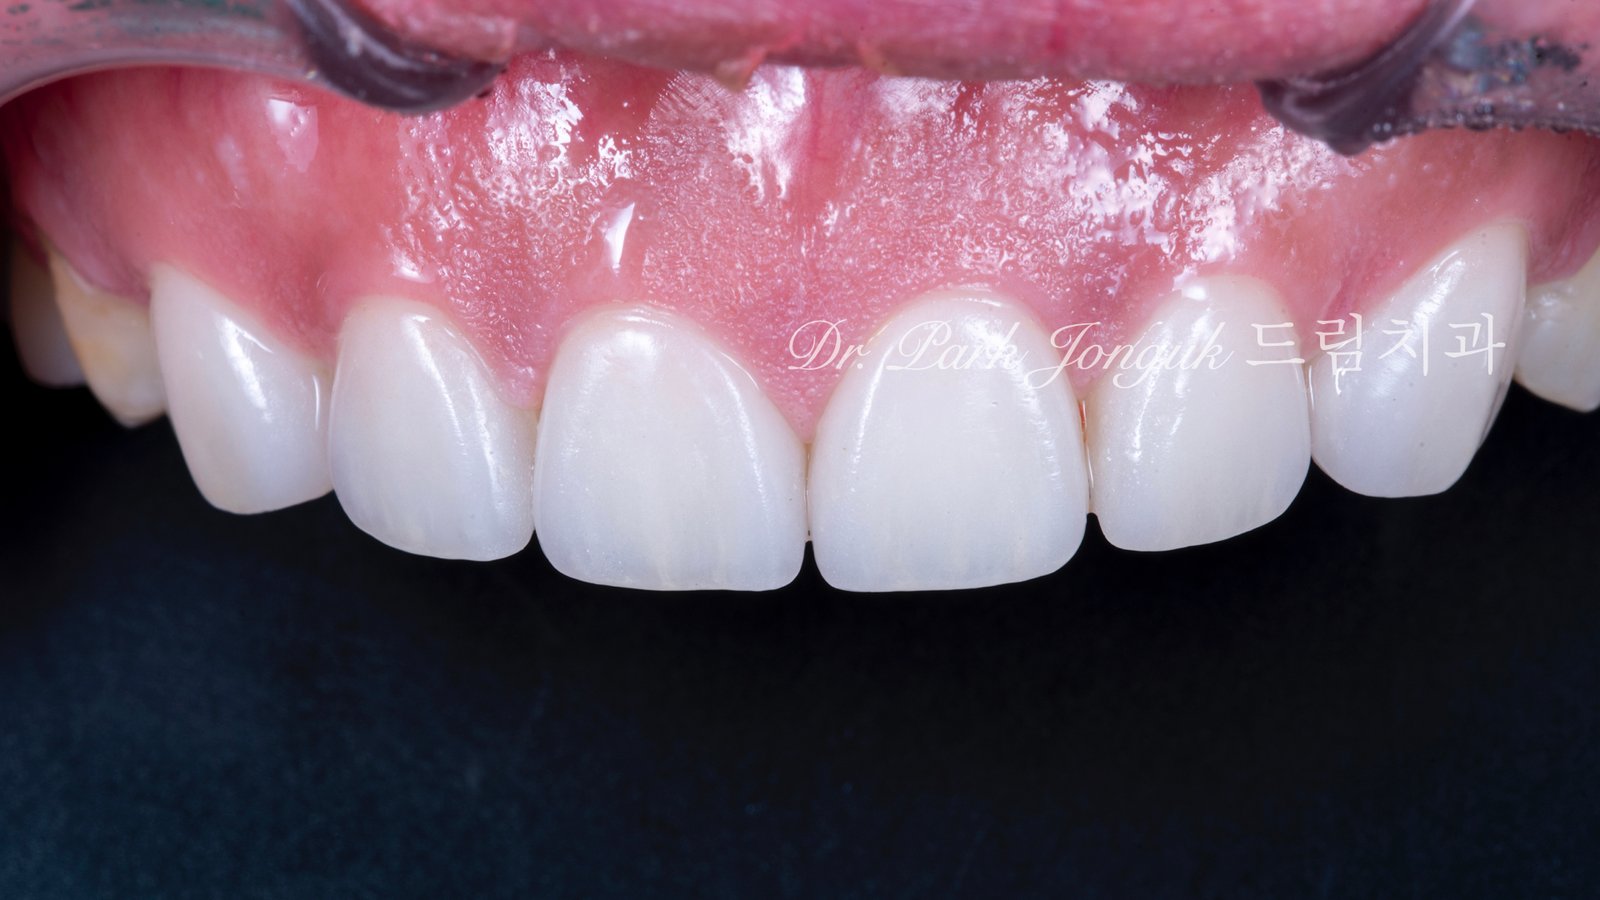

5. 최종 복원: 자연미의 극대화 (사진 6, 7, 8)

5.1 무삭제 라미네이트의 완성

[사진 6, 7, 8 참조] 0%의 삭제율로 완성된 최종 결과물입니다.

- 기능적 보호: 위산에 의해 약해진 치아 표면을 강도 높은 세라믹이 보호막처럼 감싸주어 추가적인 부식을 차단합니다.

- 광학적 재현: 기계로 깎아낸 Monolithic 방식이 아닌, 숙련된 기공사의 **핸드메이드 빌드업(Build-up)**을 통해 자연치 특유의 투명도와 질감을 재현했습니다.

- 심미적 조화: 교정으로 바르게 정렬된 치열 위에 정밀 설계된 라미네이트가 더해져, 부자연스러운 돌출감 없이 조화로운 미소를 완성했습니다.